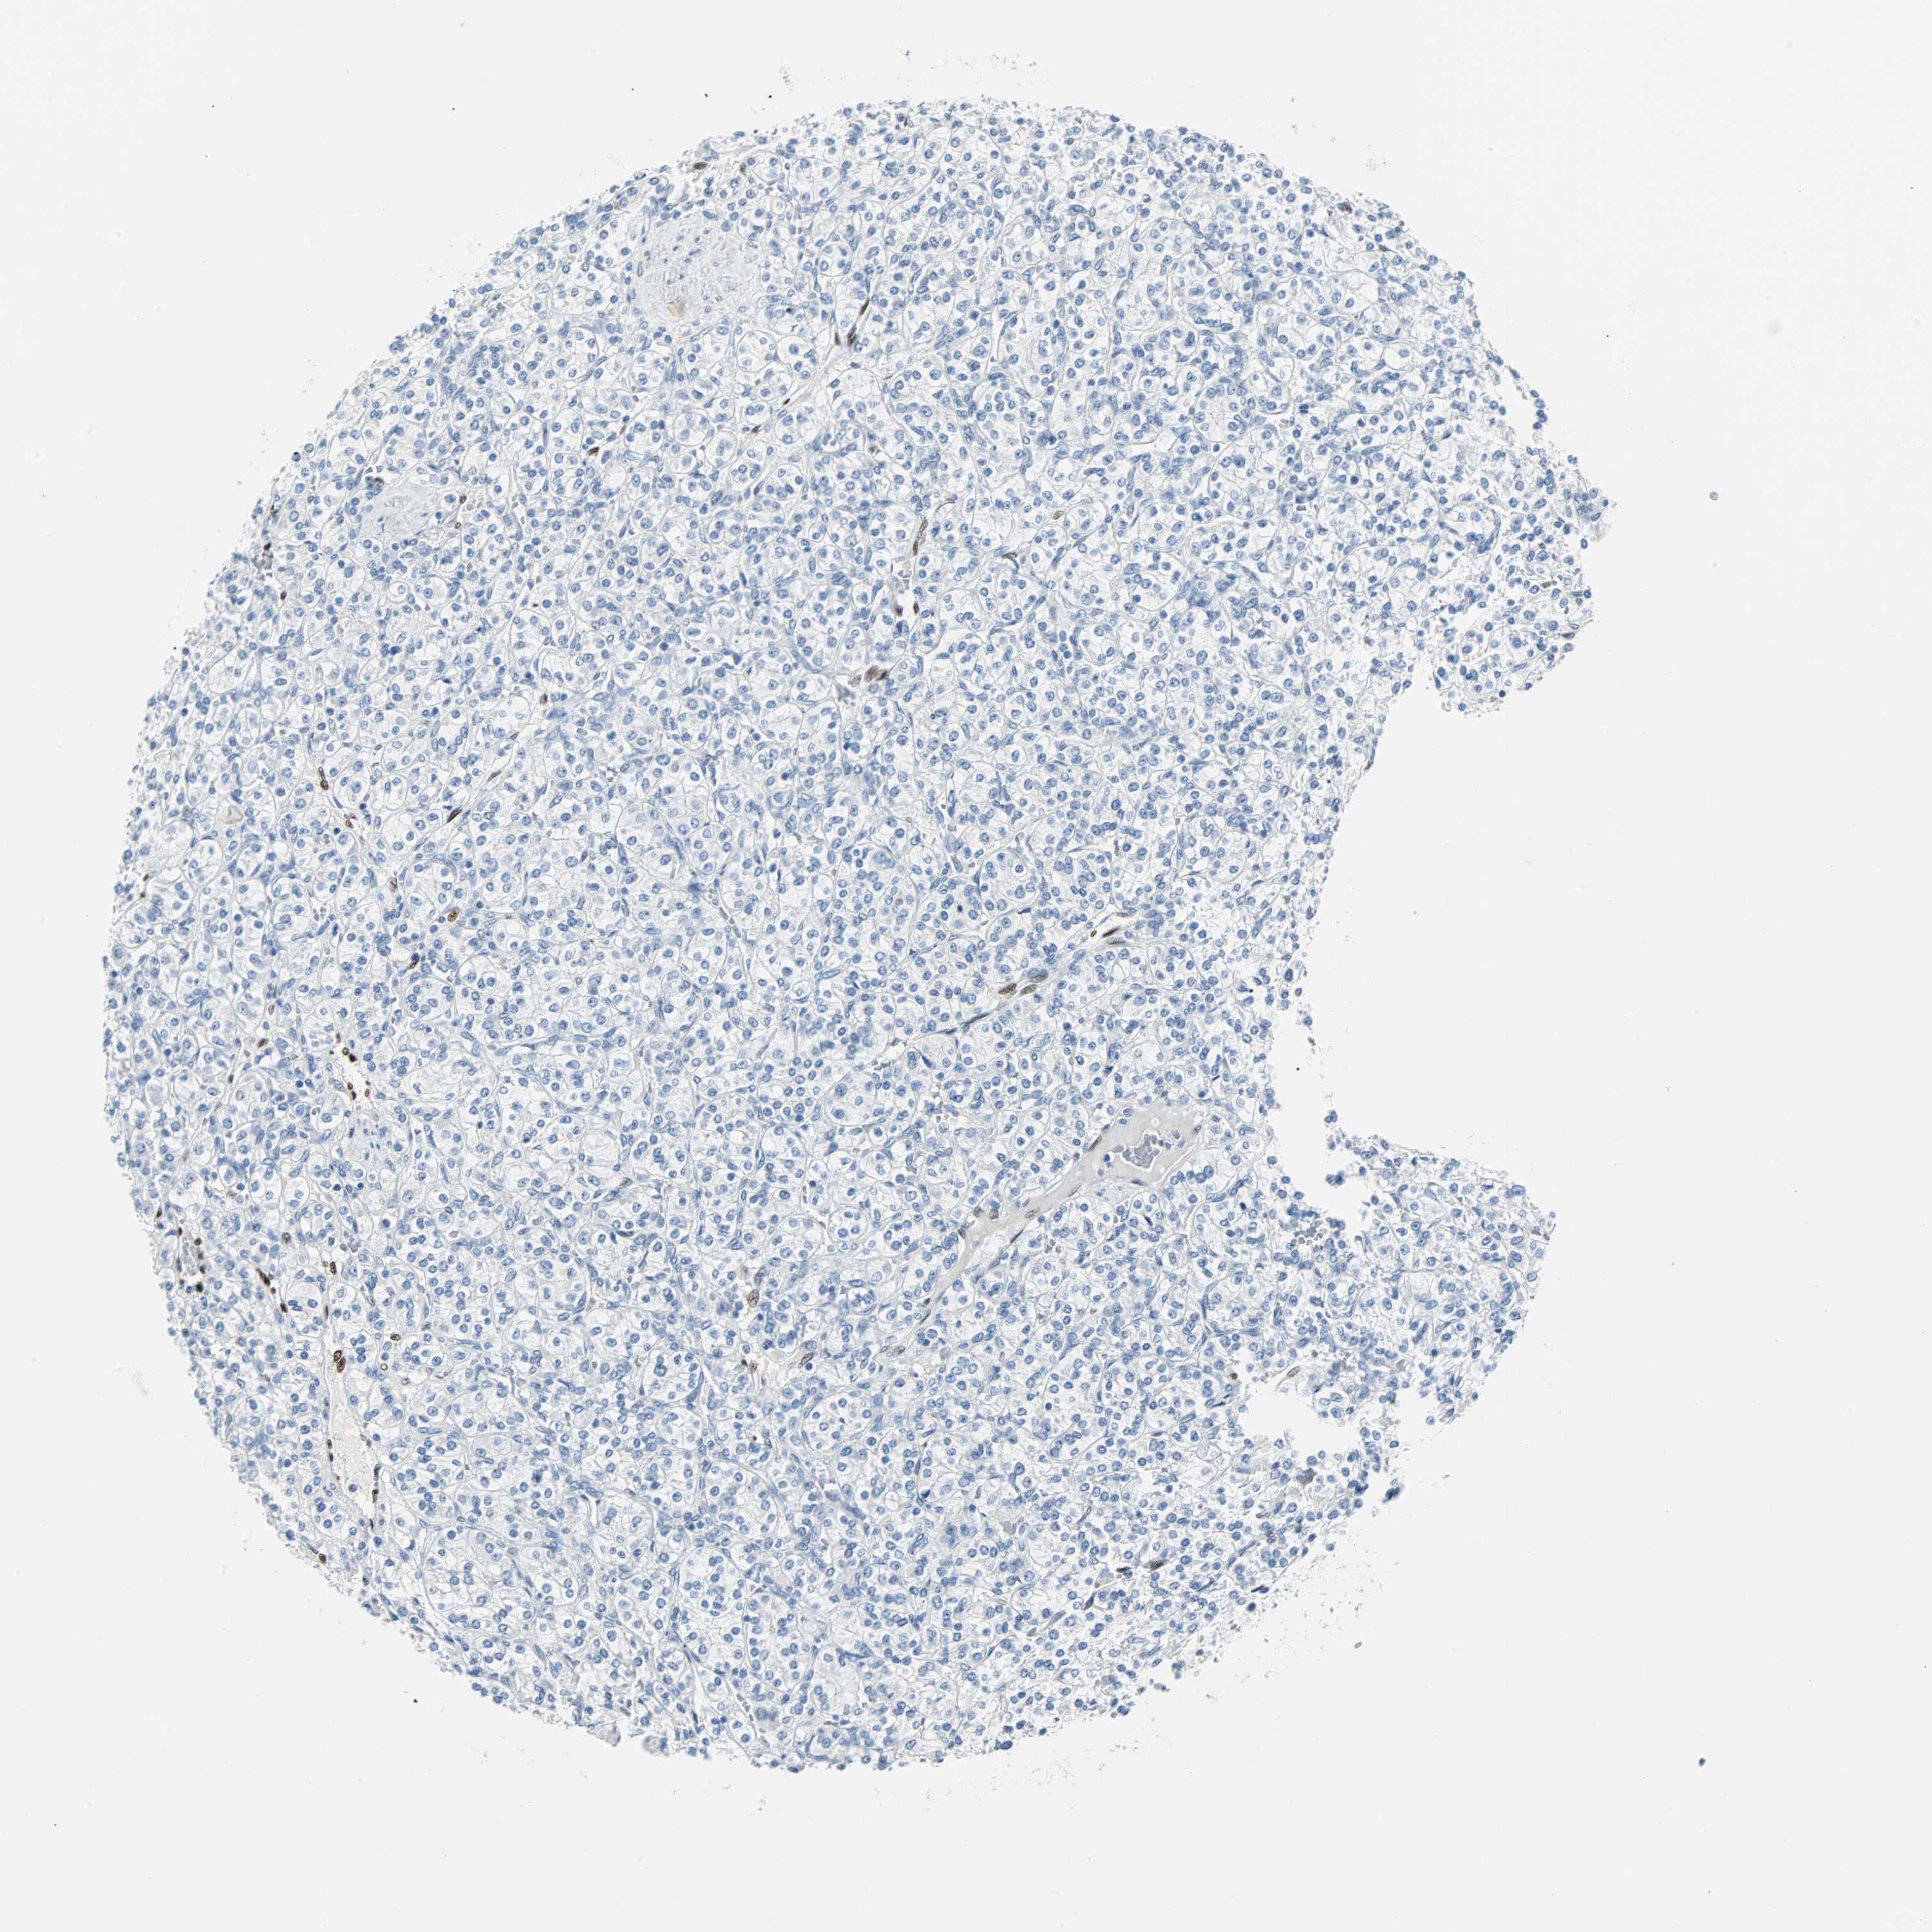

KIDNEY RENAL CLEAR CELL CARCINOMA (TCGA) - Interactive survival scatter ploti

The Survival Scatter plot shows the clinical status (i.e. dead or alive) for all individuals in the patient cohort, based on the same data that underlies the corresponding Kaplan-Meier plots. Patients that are alive at last time for follow-up are shown in blue and patients who have died during the study are shown in red.

The x-axis shows the expression levels (FPKM) of the investigated gene in the tumor tissue at the time of diagnosis. The y-axis shows the follow-up time after diagnosis (years). Both axes are complimented with kernel density curves demonstrating the data density over the axes. The top density plot shows the expression levels (FPKM) distribution among dead (red) and alive patients (blue). The right density plot shows the data density of the survived years of dead patients with high and low expression levels respectively, stratified using the cutoff indicated by the vertical dashed line through the Survival Scatter plot. This cutoff is automatically defined based on the FPKM cutoff that minimizes the p-score. The cutoff can be changed by dragging the vertical line or by entering a cutoff value in the square labeled "Current cut-off".

Under the Survival Scatter plot the p-score landscape (black curve; left axis) is shown together with dead median separation (red curve; right axis). Dead median separation is the difference in median mRNA expression between patients who have died with high and low expression, respectively. It is calculated as follows: median FPKM expression of dead patients with high expression - median FPKM expression of dead patients with low expression. This is intended to aid the user in visually exploring custom cutoffs and the associated p-scores and dead median separation.

Individual patient data is displayed and can be filtered by clicking on one or more of the category buttons on the top of the page. Categories describing expression level and patient information include: high, low, alive, dead, female, male and tumor stages. The scale of the x-axis can be toggled between linear and log-scale by clicking on the "x log" button. Mouse-over function shows TCGA ID, patient information and mRNA expression (FPKM) for each patient.

& Survival analysisi

Kaplan-Meier plots summarize results from analysis of correlation between mRNA expression level and patient survival. Patients were divided based on level of expression into one of the two groups "low" (under cut off) or "high" (over cut off). X-axis shows time for survival (years) and y-axis shows the probability of survival, where 1.0 corresponds to 100 percent.

IL33 is potential prognostic, high expression is favorable in Kidney Renal Clear Cell Carcinoma (TCGA)

Best expression cut offi

: 4.07

P scorei

N/A

Average pTPM 9.7

Number of samples 521